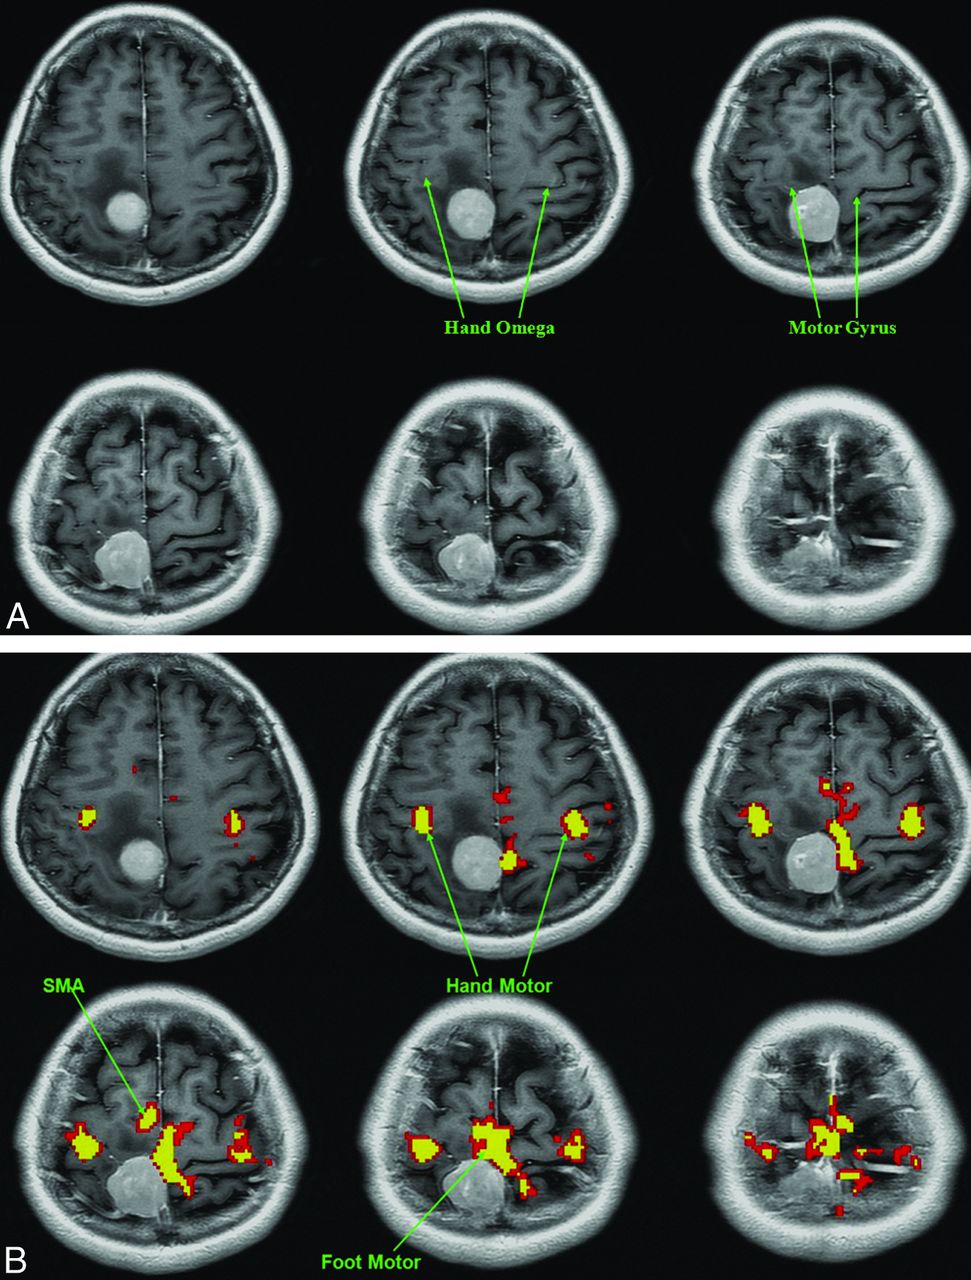

One of the more difficult cases for the raters was patient 13 (Figure). The average distance from the foot motor center in arrow placement was 16 mm in those with fMRI experience and 23 mm in those without experience. Sixty-five percent of raters with fMRI experience and 50% of raters without fMRI experience placed the arrow in the correct gyrus. Eighteen percent and 33% of raters with and without fMRI experience respectively, correctly identified the tumor as not being located in the foot motor cortex. Last, 35% and 39% of raters with and without fMRI experience, respectively, correctly identified the tumor as not being located in the motor gyrus.

Axial T1-weighted without (A) or with (B) coregistered functional MR images obtained during a bilateral finger-tapping and foot motor paradigm. The raters were asked to identify the foot motor homunculus solely on the basis of the anatomic images (A) without the benefit of fMRI (B). fMRI places the extra-axial lesion just posterior to the primary motor gyrus, including the foot motor portion of the motor homunculus. Edema extends to involve both the precentral and postcentral gyri. The average arrow placement from the foot motor center was 16 mm in those with fMRI experience and 23 mm in those without it. A higher percentage of raters with fMRI experience than those without it placed the arrow in the motor gyrus (65% versus 50%). Eighteen percent of raters with fMRI experience correctly identified the tumor as not being located in the foot motor cortex, while 33% of raters without fMRI experience did so. Last, 35% and 39% of raters with and without fMRI experience, respectively, correctly identified the tumor as not being located in the motor gyrus. Most of the incorrect arrow placements were due to the arrow being placed in a gyrus posterior to the motor gyrus.